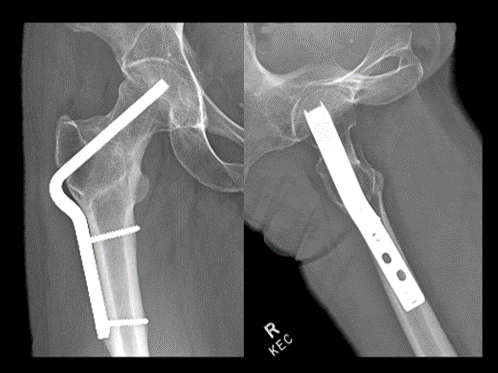

Post-op xrays after the procedure. The overall alignment of the hip has been restored. The patient is given crutches and toe-touch restrictions for 6 weeks #postop #traumacase #orthopaedics